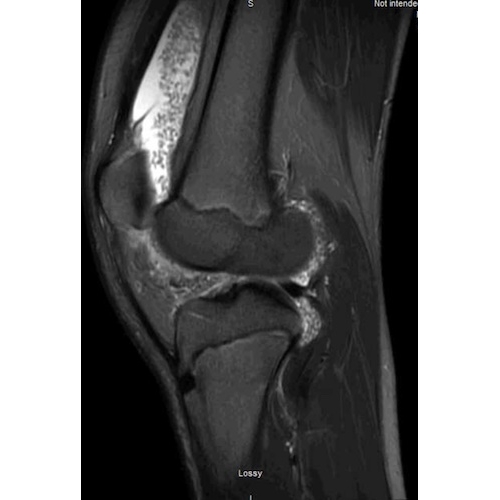

| A Knee Full Of Surprises - Page #3 | |||